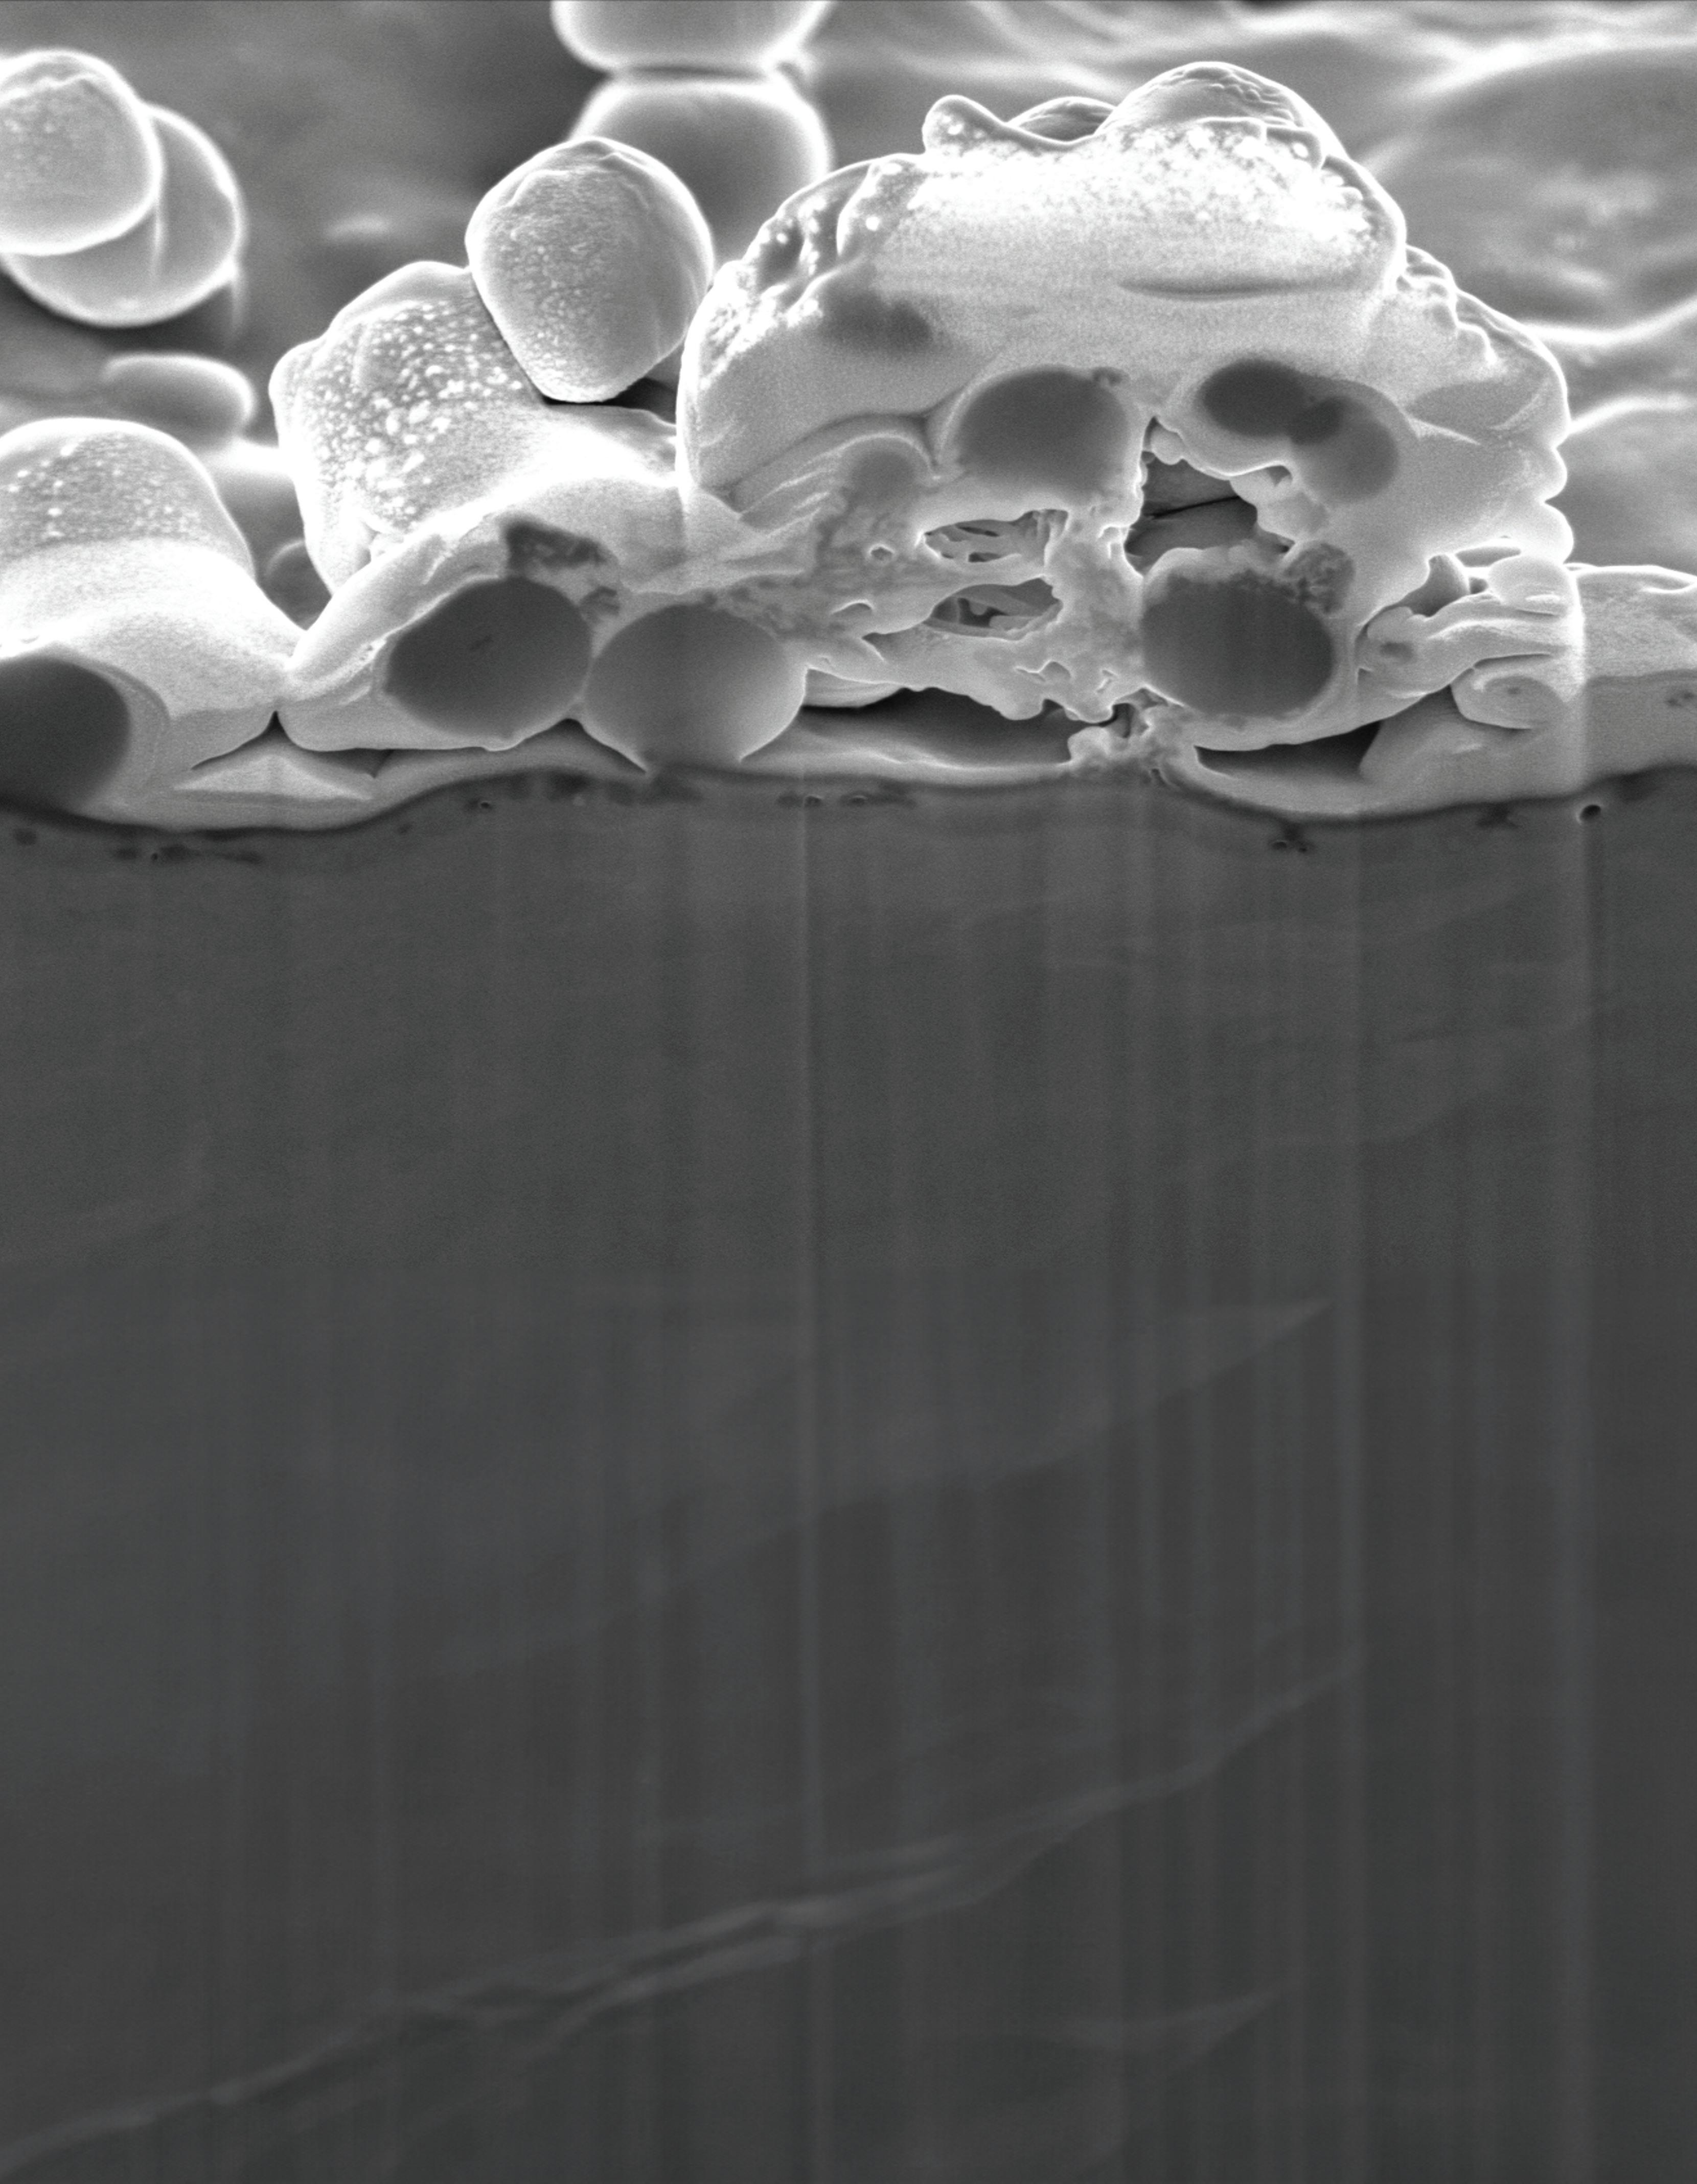

This scanning electron microscope image shows Orthobond’s Ostaguard antimicrobial coating killing methicillin-sensitive Staphylococcus aureus (MSSA) bacteria.

Image courtesy of Orthobond

The resulting layer of positively charged, quaternary ammonium molecules on an implant’s surface measures only one-millionth of an inch and immobilizes, perforates and destablizes microbes.

“It’s like flypaper because bacteria is negatively charged and our surface is positively charged,” Nichols said. “It actually draws them to our surface, puts little pin pricks in the bacteria and starts the death process. As they try to move around, it breaks them apart and kills them.”